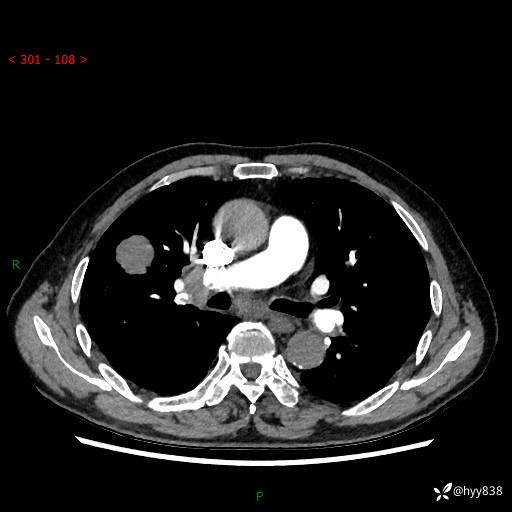

69岁/男,间断咳嗽伴气促、下肢水肿。临床拟诊肺栓,偶发肺均质强化结节--结果公布

【患者信息】:69岁/男

【主诉】:间断咳嗽伴气促、下肢水肿2周

【现病史及既往史】:患者2周来无明显诱因出现咳嗽,咳少量白痰,不易咳出,伴有气促,呈间断发作,症状与活动费力相关,以夜间为甚,不能平躺入睡,偶有憋醒,无胸闷胸痛、无发热、无头晕、头痛等不适,伴有双下肢中度水肿,就诊于当地县人民医院门诊,完善相关检查提示:左下肢深静脉血栓形成,未予以特殊处理,今患者为求进一步诊治来我院就诊,拟“心衰”收入我科。 起病以来,患者精神、饮食、睡眠可,大小便如常,体力明显下降,体重未见明显减轻。

【检查】:胸部CT增强